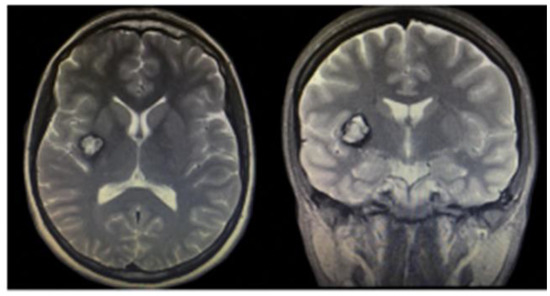

3.1.2. Brain Cavernous Angiomas

3.2. Arteriovenous Malformation (AV Angioma, Cirsoid Angioma)